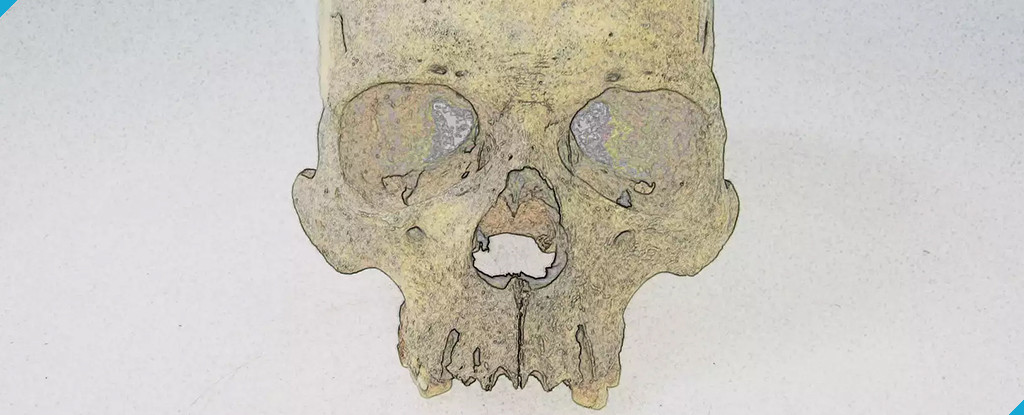

Un misterioso patógeno de la lepra ha acechado en América durante 4 000 años

Un misterioso patógeno de la lepra ha acechado en América durante 4 000 años